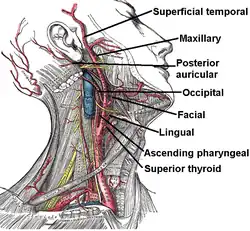

Branches

As the artery travels upwards, it gives the following branches:

- In the carotid triangle:[3]

- Superior thyroid artery, arising from its anterior aspect

- Ascending pharyngeal artery - arising from medial, or deep, aspect

- Lingual artery - arising from its anterior aspect

- Facial artery - arise from its anterior aspect

- Occipital artery - arising from its posterior aspect

- Posterior auricular artery - arising from posterior aspect

The external carotid artery terminates as two branches:

The superior thyroid artery anastomoses with inferior thyroid artery, where the latter arises from thyrocervical trunk of the subclavian artery.[2]

Terminal branch of facial artery anastomose with ophthalmic artery of internal carotid artery.[2]

Posterior auricular artery anastomose with occipital artery, another branch of external carotid artery.[2]

One of the branches of superficial temporal artery anastomose with lacrimal and palpebral branches of ophthalmic artery.[2]

Branches of external carotid artery

Branches of external carotid artery